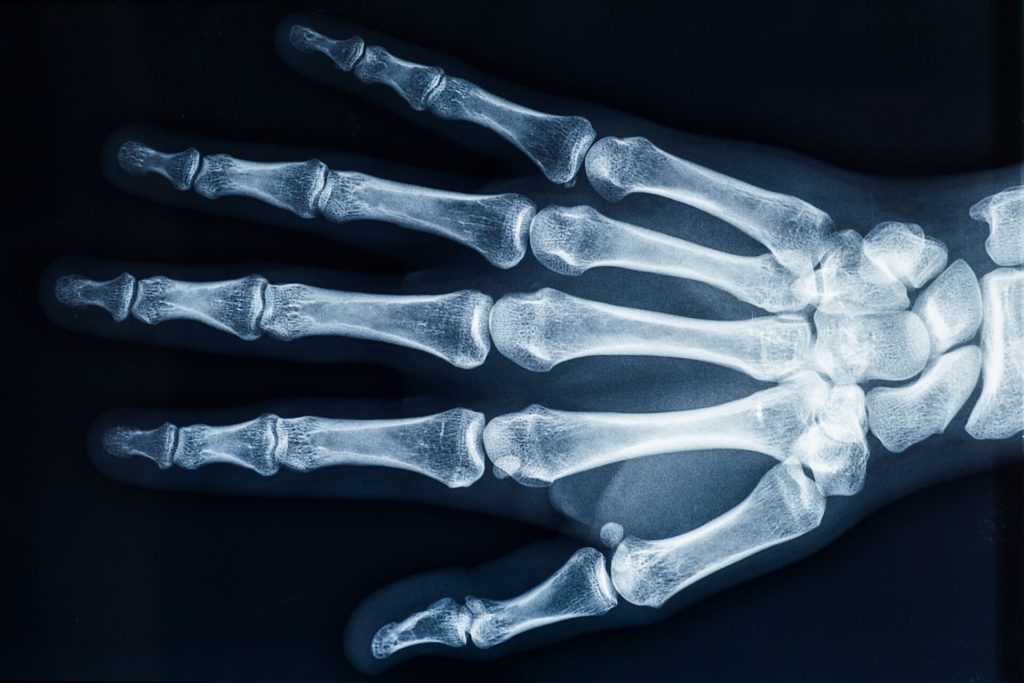

Suggest X-ray

Finger arthritis is an inflammatory disorder that can occur in many different ways. It can be systemic where your body will attack itself in the case of Rheumatoid Arthritis (RA) or it may occur as a result of wear and tear, Osteo Arthritis (OA). While both of these conditions are painful and involve swelling and the de generation of the cartilage insie the joints of the finger, their cause is very different. At Action Rehab our Hand Therapists assess and treat a majority of patients who suffer from Osteo Arthritis (wear and tear of the joints) which often occurs as a result of a sporting or repetitive job or task such as gardening. This type of arthritis is very common and can be easily treated. Finger arthritis is painful and it is debilitating and can cause deformities if left untreated. At Action Rehab our Hand Therapists, Physiotherapists and Occupational Therapists are experienced in reading x-rays and assessing your hand for arthritis and joint degeneration.